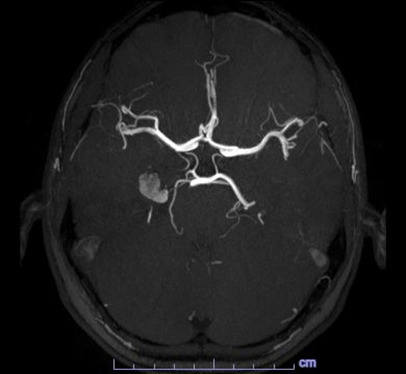

With the diagnosis not clear, an MRA with contrast was obtained the next day which revealed a 1.2 cm lesion involving the medial right temporal lobe, the radiologist favored a cavernous hemangioma but could not completely rule out an aneurysm as the lesion is very hyperintense on T1-weighted images (figs.5 and 6).